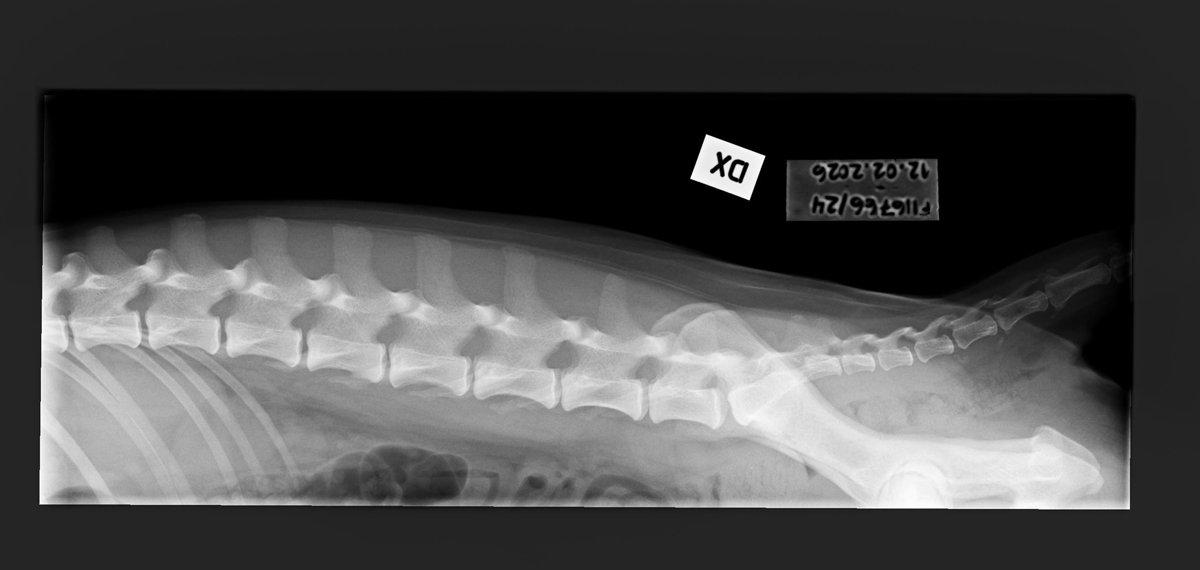

- Finnish Kennel Club's elbow x-ray report Dec '25: Signs suggestive of medial coronoid disease; further information about the condition of the joints can be obtained, if necessary, by computed tomography (CT) examination

- Finnish Kennel Club's elbow CT report Feb '26: A small amount of new bone formation around the medial coronoid process of the left elbow

- Free of lumbosacral transitional vertebrae (LTV0)

- Free of spondylosis (SP0)

- Free of vertebral anomalies (VA0)

- Spine x-rays: 1, 2 ja 3